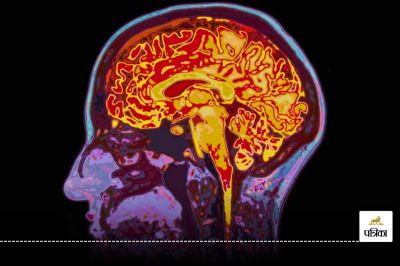

डिमेंशिया (Dementia) एक ऐसी स्थिति है जिसमें व्यक्ति की याददाश्त, सोचने की क्षमता और समस्या हल करने की क्षमता कमजोर हो जाती है। इसका सबसे आम कारण अल्जाइमर रोग है, लेकिन डायबिटीज (Diabetes) भी इस मानसिक गिरावट का एक प्रमुख कारण बन सकता है। इस बीमारी में लोग अपना नाम, पता या रोज़मर्रा की महत्वपूर्ण जानकारी भूलने लगते हैं।

विशेषज्ञों का कहना है कि टाइप 2 डायबिटीज (Type 2 Diabetes) से पीड़ित लोगों में डिमेंशिया (Dementia) होने का खतरा अधिक रहता है। इसका कारण यह है कि इस प्रकार की डायबिटीज में इंसुलिन ठीक से काम नहीं करता, जिससे रक्त में ग्लूकोज का स्तर बढ़ जाता है। यह बढ़ा हुआ ग्लूकोज मस्तिष्क की कोशिकाओं को नुकसान पहुंचाता है, जिससे डिमेंशिया की संभावना बढ़ जाती है।

टाइप 2 डायबिटीज(Type 2 Diabetes) मस्तिष्क में सूजन पैदा कर सकती है, जो डिमेंशिया (Dementia) के विकास में सहायक हो सकती है। साथ ही, डायबिटीज की वजह से मस्तिष्क को पर्याप्त ऑक्सीजन नहीं मिल पाती, जिससे मस्तिष्क की कोशिकाएं कमजोर हो जाती हैं और धीरे-धीरे उनका कार्यक्षमता कम हो जाती है।

कुछ शोधों में यह पाया गया है कि डायबिटीज मस्तिष्क में एमीलॉइड प्रोटीन के संचय को बढ़ावा देती है। यह वही प्रोटीन है जो अल्जाइमर रोग के लक्षणों से जुड़ा होता है। इस कारण डायबिटीज से पीड़ित लोगों में अल्जाइमर और अन्य डिमेंशिया (Dementia) रोगों का खतरा बढ़ सकता है।